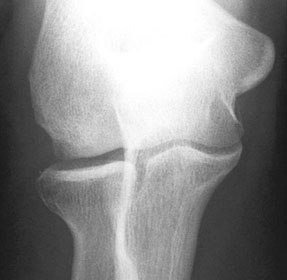

2.自家骨軟骨移植法(モザイクプラスティー)

膝関節の中でも後遺症を残しにくい部分(大腿骨滑車部)から、自分の正常な軟骨を骨ごと採取し、これを膝関節や肘関節の軟骨が損傷した部位に移植する方法です。

モザイクプラスティー前

モザイクプラスティー後